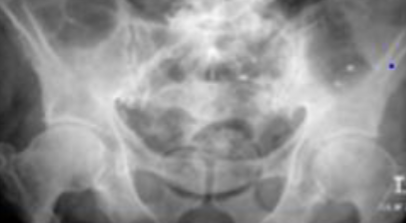

Q1: Name the (A) imaging study and (B) mention the main abnormality. (A) Erect chest X-ray. (B) Air under the diaphragm (pneumoperitoneum).

Q2: Name TWO clinical conditions where you can get this finding:

- Perforated bowel,

- post operative,

- injury as knife injury

1-x-ray showing air fluid level

Finding: Air fluid level

DDx: Post operative, perforated viscus, penetrating trauma

Laboratory investigation: CBC, LFT

Management: NPO, NG tube, IV fluids

Chest X-ray image obtained from a patient

Q1: What is your finding? Free air under diaphragm

Q2: Name TWO causes of this abnormality. Perforated duodenal ulcer, Penetrating trauma

Large bowel obstruction

1- What is imaging technique? X-ray

2- what is your findings? Dilated + obstructive intestine

Mention 4 causes of this condition? Neoplasm, volvulus, polyp, hernia, adhesions, intussusception